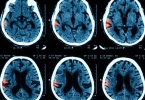

脑梗塞灶能否治好取决于梗塞灶的大小、位置以及治疗时机,多数患者通过及时治疗可以改善症状并减少后遗症。脑梗塞灶的治疗效果与发病后就医时间密切相关。在发病后3-4.5小时内接受静脉溶栓治疗,部分患者血管可再通 ...

多发性脑梗塞可能由高血压、动脉粥样硬化、心脏病、糖尿病、血液高凝状态等原因引起。多发性脑梗塞通常表现为肢体麻木、言语障碍、头晕头痛、吞咽困难、认知功能下降等症状。可通过控制基础疾病、抗血小板治疗、康复 ...

脑梗塞后腿功能障碍的恢复程度与梗死部位、治疗时机及康复干预有关,部分患者通过规范治疗可改善功能,但严重损伤可能遗留永久性运动障碍。脑梗塞导致的运动功能障碍主要涉及大脑运动皮层或传导通路损伤,需结合药物 ...

左额叶脑梗塞可通过溶栓治疗、抗血小板聚集治疗、神经保护治疗、康复训练、手术治疗等方式治疗。左额叶脑梗塞通常由动脉粥样硬化、心源性栓塞、小动脉闭塞、血液高凝状态、血管炎等原因引起。1、溶栓治疗溶栓治疗是 ...